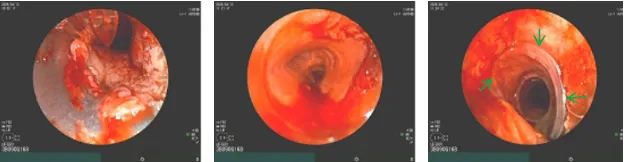

术中气管镜探查发现,气管上段瘘口处脓性分泌物附着,周围气道组织结构紊乱。由于刘大爷本身存在右侧声带麻痹,支架放置的位置必须精确到毫米:放得高了,会压迫声门影响发音;放得低了,封不住瘘口。

赵文飞主治医师沉稳操控硬质镜,建立通道,清理病灶。孙丽娟主任医师与团队成员紧密协作,将压缩在输送管内的硅酮支架送入硬质镜。随着推入器缓缓进入,支架在预定位置精准展开。

那一刻,原本塌陷狭窄的气道被瞬间撑开,致命的“黑洞”消失在视野中,取而代之的是光滑、通畅的硅酮壁。手术宣告圆满成功!